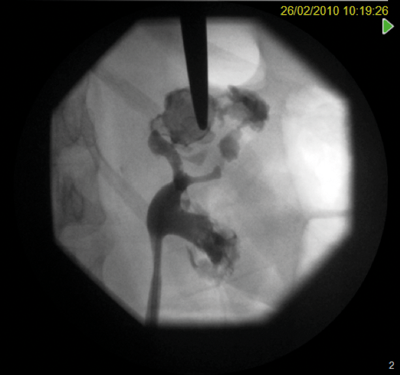

Percutaneous nephrolithotomy (PCNL) failed. Although the calyx was successfully punctured, due to the lack of overlying cortex, no track could be established.

Marking for PCNL access.